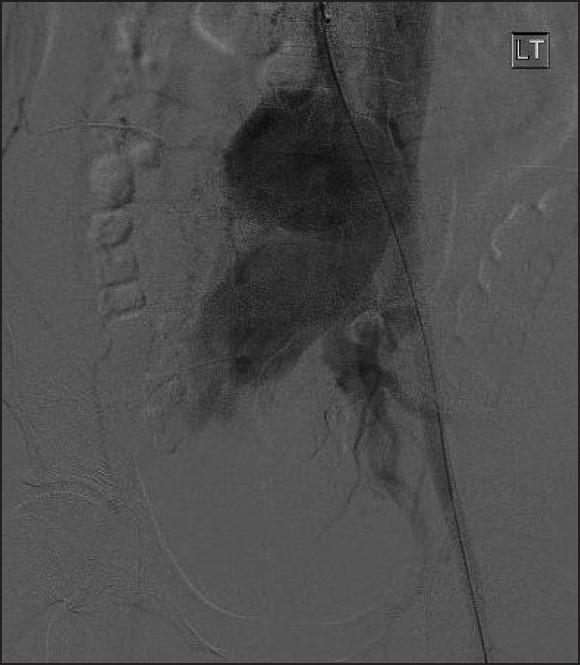

Vascular complications during posterior lumbar disc surgery are rare and its presentation with varicose veins is even rarer. A 23 year-old male patient presented with large varicose veins in right lower limb. He underwent a posterior lumbar spine discectomy surgery. He noticed mild swelling of the distal third right lower limb 3 months after index surgery and reported 6 months later when he developed varicose veins. Duplex Doppler confirmed varicose veins of the long saphenous vein and its tributaries with a patent deep venous system. A digital subtraction angiogram demonstrated a large right common iliac artery (CIA) false aneurysm with an arteriovenous fistula between right common iliac vessels. He had a right CIA covered stent insertion with good results. Varicose veins were later managed with sapheno-femoral junction ligation and a below knee long saphenous vein stripping. At six month follow-up the lower limb swelling had completely recovered and duplex ultrasound did not show any recurrence of varicose veins.

https://cdn.ncbi.nlm.nih.gov/pmc/blobs/81da/3227363/2b1d94786bce/IJOrtho-45-563-g002.jpg

https://cdn.ncbi.nlm.nih.gov/pmc/blobs/81da/3227363/88594f5cc30d/IJOrtho-45-563-g001.jpg